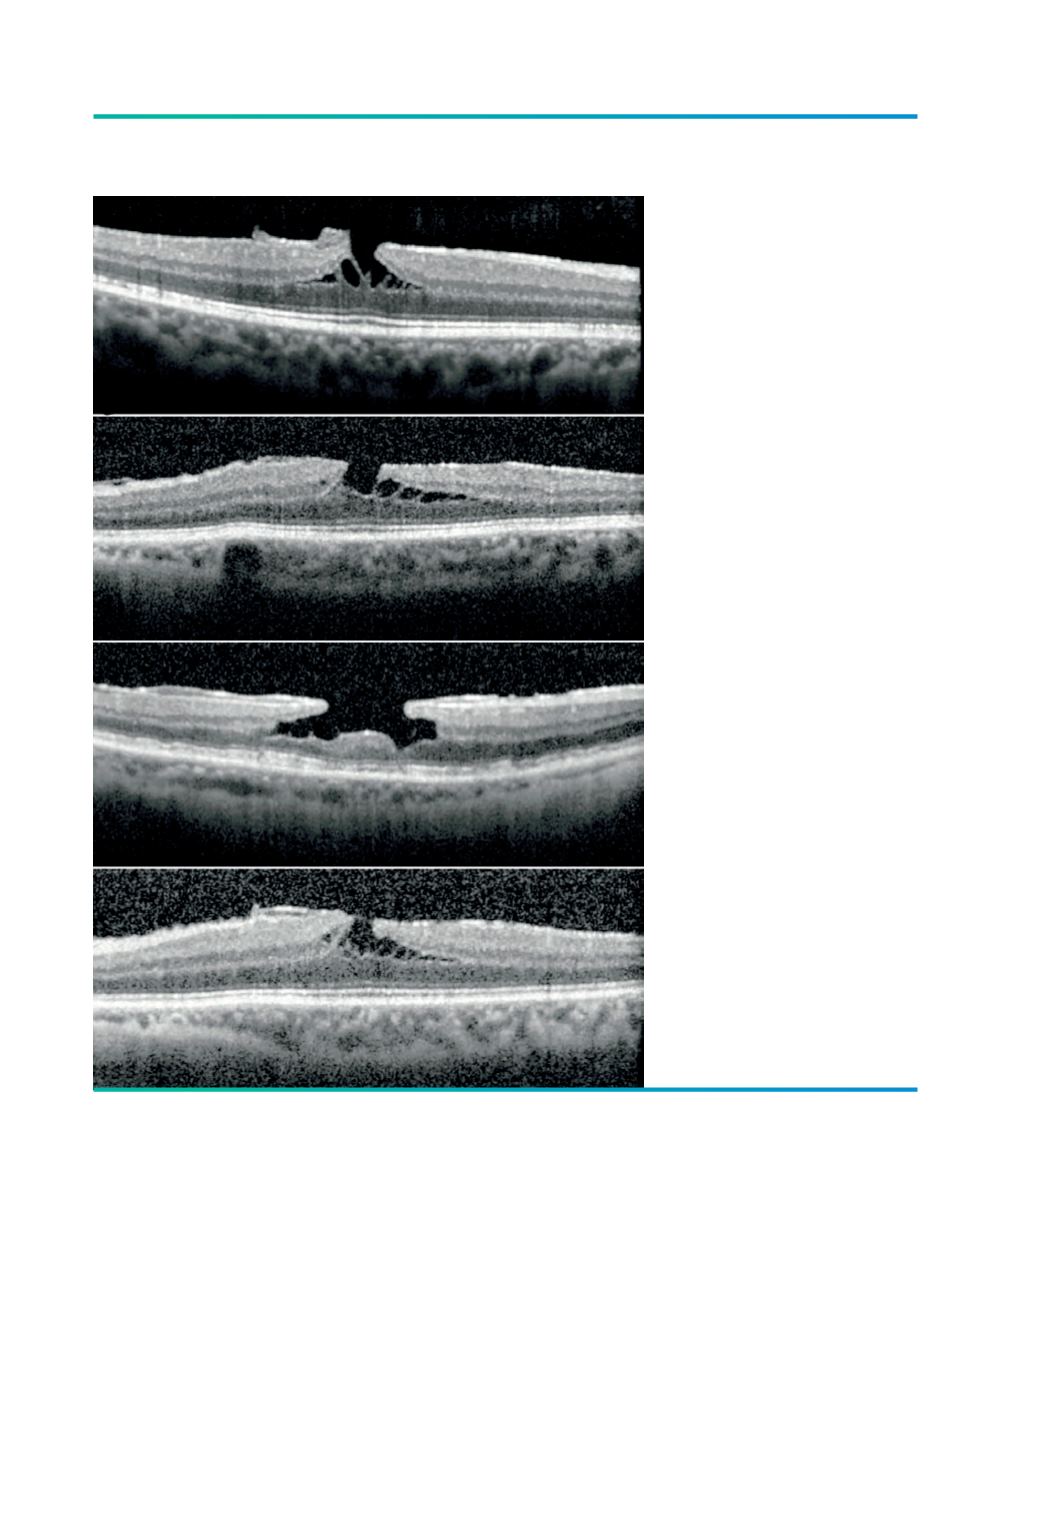

Figura 1.

Imagens de SD-OCT de buracos

lamelares com as alterações

anatómicas características:

A) Contorno foveal irregular; B)

Defeito a nível das camadas

internas da fóvea; C) Separação

horizontal intrarretiniana entre

a camada plexiforme externa

e camada nuclear externa; D)

Camada de fotorreceptores

intacta.

A

B

C

D